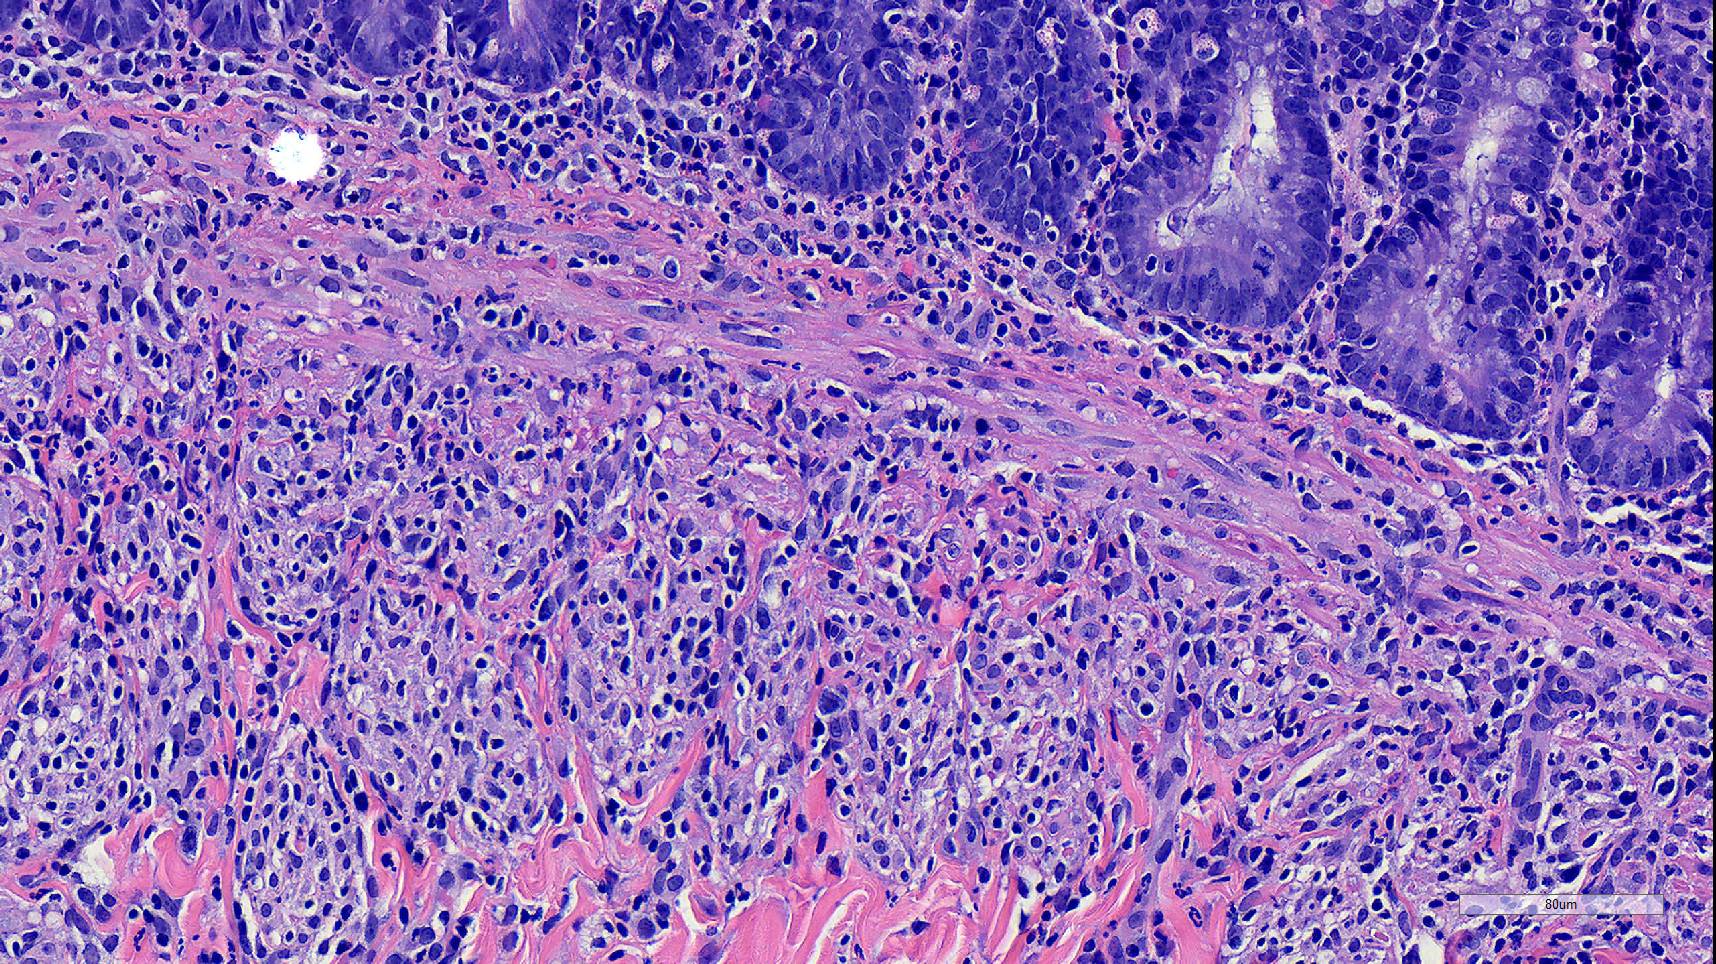

Microscopic Description:

Duodenum, jejunum and ileum: Diffusely throughout the sections, there is partial to complete loss of the leiomyocytes of the outer and inner muscularis, which are multifocally replaced by loose fibrous connective tissue (fibrosis). The remaining smooth muscle is infiltrated by large numbers small and intermediate lymphocytes, few macrophages and neutrophils. The same inflammatory infiltrate is present throughout the muscularis mucosae. Remaining leiomyocytes have pale, frequently vacuolated cytoplasm. In the submucosa, muscularis and serosa there are small to moderate numbers of perivascular lymphocytes. Small lymphocytes, and infrequently neutrophils, surround or infiltrate the myenteric and submucosal ganglia, though neurons do not exhibit degenerative changes. The lamina propria contains a markedly increased number of lymphocytes, plasma cells and a mildly increased number of eosinophils. The epithelium is diffusely overlain by myriad bacterial rods. The serosa is mildly expanded by increased clear space (edema) and is lined multifocally by markedly hypertophied mesothelium. In the stomach a similar process is observed but restricted to the outer aspect of the muscularis with a patchy/multifocal distribution and sparing of the muscularis mucosae. (section not submitted).

Duodenum, jejunum and ileum: Severe, diffuse, chronic lymphocytic leiomyositis with severe muscularis atrophy; marked, diffuse, chronic lymphoplasmacytic enteritis.

Microscopic findings reported for this condition consist of mild to marked mononuclear infiltrate, myofiber degeneration and fibroplasia or fibrosis centered within the muscularis propria of the stomach, small and large intestinal wall with the jejunum being the most severely and chronically affected segment.7,15 In early lesions the inflammation and smooth muscle degeneration are segmental, random between the outer and inner muscularis layers and sparing of the muscularis mucosae.15 Concurrent cecal involvement leading to impaction has also been described.5 Consistent histologic findings included T-lymphocyte inflammation within the muscularis propria with relative sparing of the mucosa, submucosa and neural plexuses.14 In one case report the inflammatory infiltrate was predominantly of B-lymphocytes and featured extensive angiogenesis.6 Leiomyocytes appear to be the target of the inflammation given the presence of various stages of degeneration leading to complete myofiber loss in chronic stages of the disease. Superficial inflammation is a frequent secondary finding in CIPO and has been associated with bacterial overgrowth, which were changes observed in this case.6 Neuropathy has not been a feature in most reports of canine CIPO. Inflammatory cells obscuring the myenteric and submucosal plexuses in this case were considered an extension from the neighboring inflammation as no degenerative changes were observed in the neurons. Myenteric ganglionitis has, however, been reported occurring concurrently with leiomyositis.10

The pathogenesis for this condition remains unclear, though the targeting of smooth muscle by T-lymphocytes is supportive of a cell-mediated inflammatory process suggestive of an immune-mediated process against intestinal smooth muscle.11,14,15 In humans with intestinal leiomyositis, the inflammation is specific for the intestinal musculature as leiomyocytes of vessels or other tissues are unaffected.15 Humans with intestinal leiomyositis can have autoimmune disease as a preexisting condition, including systemic lupus erythematosus, rheumatoid arthritis, scleroderma, and autoimmune hepatitis.7 Neither the dog in this case nor those in the largest case series in dogs with leiomyositis had concurrent evidence of systemic autoimmune disease.14 In few human cases, acute episodes of infectious gastroenteritis or diarrhea preceded the development of gastrointestinal distention.7 Molecular mimicry has been proposed as a mechanism for the development of leiomyositis, although an explanation of restriction of the inflammation to the gastrointestinal tract was not elucidated.7

Small intestine: Leiomyositis, lymphocytic, chronic, diffuse, severe, with marked smooth muscle loss and fibrosis.